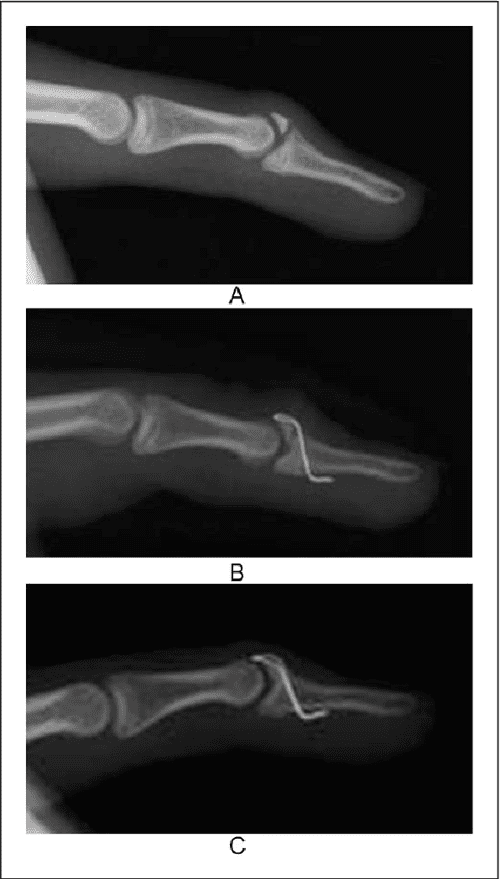

Figure 4 from Mallet fingers with bone avulsion and DIP joint Mallet Finger Bruising mallet finger, also known as baseball finger or drop finger, is a condition where the tendon that straightens the tip of the. the finger is usually painful, swollen, and bruised. The injury should be seen by a doctor. The fingertip will straighten only if you push it up with your other hand. The fingertip will droop noticeably. Usually,. Mallet Finger Bruising.

Treatment of mallet fractures with a transverse twohole mini plate Mallet Finger Bruising A bump may appear just below the nail on the back of the finger. The injury should be seen by a doctor. Blood can collect beneath the nail, and the. The fingertip will droop noticeably. Fingernail detached from the nail bed. the finger is usually painful, swollen, and bruised. the finger may be painful, swollen, or bruised. . Mallet Finger Bruising.